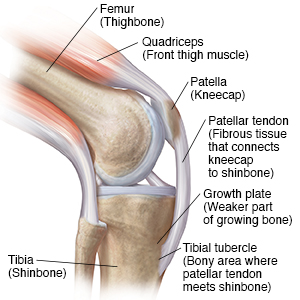

Understanding Osgood-Schlatter Disease: Anatomy

Your knee is a complex joint with many parts. These parts work together to give you the flexibility and motion needed for walking, running, and jumping. But with Osgood-Schlatter disease, knee pain can leave you on the sidelines. Osgood-Schlatter disease is an overuse injury that affects children and adolescents who play sports. It occurs more frequently in athletes who participate in sports that involve running and jumping, including:

A knee with Osgood-Schlatter disease

When your leg moves, the thigh muscle pulls the kneecap. Next, the kneecap pulls a tough band of connective tissue. This tissue then pulls on a bony area at the top of your shinbone.

In some kids, all that pulling can cause Osgood-Schlatter disease. This causes pain and often swelling on the front of the knee.

The symptoms may limit your activities. This is because the pulling happens in an area of the bone that’s still growing. As a rule, growing parts of a bone are weaker than other parts. This makes the growing area more likely to get injured.